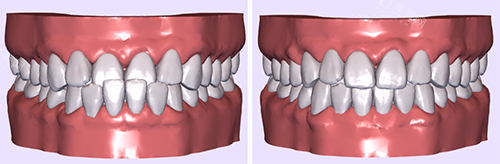

在矫正效率方面,自锁牙套展现出了强大的优势。它能够实现轻力持续矫正,每月牙齿移动速度可达 0.8 - 1.2 毫米,相比之下,非自锁牙套的矫正力相对较弱。临床数据表明,自锁牙套的矫正系统能使疗程比非自锁牙套缩短 3 - 6 个月。对于复杂的病例,如重度拥挤或深覆盖等情况,自锁牙套逐步释放的矫治力能更好地控制牙根位置,实现更准一些的矫正。

非自锁牙套虽然在矫正效率上稍逊一筹,但它在一些需要精细调整的复杂病例中也有其独特的价值。不过,它需要频繁调整结扎力度,这可能会延长整个治疗周期。

佩戴牙套的舒适度也是很多人关注的重点。自锁牙套在这方面表现出色。其托槽的圆润边缘设计降低了口腔溃疡的风险,复诊间隔可延长至 8 - 10 周。临床数据显示,自锁牙套患者的疼痛感知强度比非自锁牙套患者降低了 40%,尤其适合青少年患者。